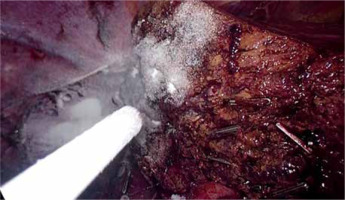

Nonetheless, in LLS, application of some TA may be challenging. Although there are no data addressing this issue, according to the clinical experience, sprays and powders are easier to apply via laparoscopy than sponge-based local TA (Photo 8).